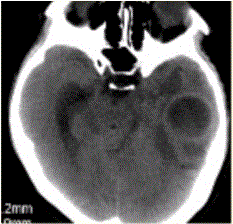

问题 患者女,26岁,头痛、低热10d余,既往有左侧慢性中耳炎病史。CT表现如下图。 MRI检查中,脑脓肿最敏感的方法或序列显示是

选项 A.T2*WI B.DWI C.FLAIR D.T2WI E.PDW

答案 B